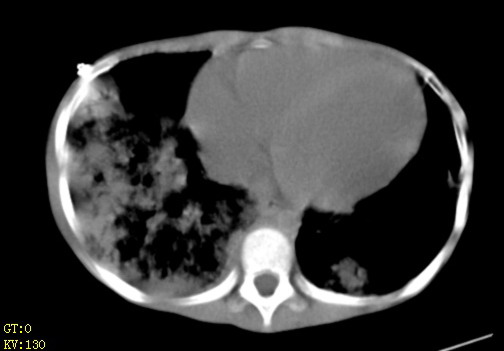

女,12岁,气促、咳嗽2天,3个月前查胸片示:两肺感染,急诊入院查ct,血常规等未检查。

双肺中下野不规则片絮状阴影,中外带明显,双侧胸腔少量积液,心影增大,心腔密度减低,隆突下及左侧气管旁见钙化淋巴结影,考虑双肺感染、心衰;建议结合临床除外h1n1并急性心衰,先心不能排除。

两肺多发片絮状模糊影,以下肺外带居多,内见支气管气像,纵膈窗未减影,两侧胸腔积液,心影增大,结合心超,支持重症肺炎,非常时期,甲型h1n1流感不排除。